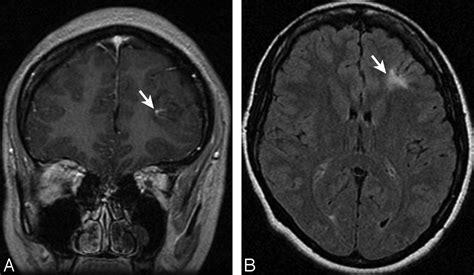

The human brain is a dynamic organ that undergoes various changes throughout a lifespan. Parenchymal volume loss, or cerebral atrophy, is essentially the loss of neurons and the connections between them. As the brain loses these cells, the physical space they occupied diminishes. This can manifest as an expansion of the sulci (the grooves on the surface of the brain) or the enlargement of the ventricles (the fluid-filled spaces inside the brain).

While often associated with neurodegenerative diseases, it is crucial to recognize that some degree of brain shrinkage is a normal part of the aging process. However, when the loss occurs at an accelerated rate or is localized to specific regions of the brain, it warrants further investigation by a neurologist to distinguish between normal age-related changes and pathological conditions.

Diagnostic Approaches and Interpretation

When a radiologist identifies volume loss, they usually assess the distribution of the atrophy. Generalized atrophy refers to widespread loss across the entire brain, while focal atrophy suggests that specific areas, such as the hippocampus or the frontal lobes, are being disproportionately affected. The following table provides a snapshot of how medical professionals categorize these findings: